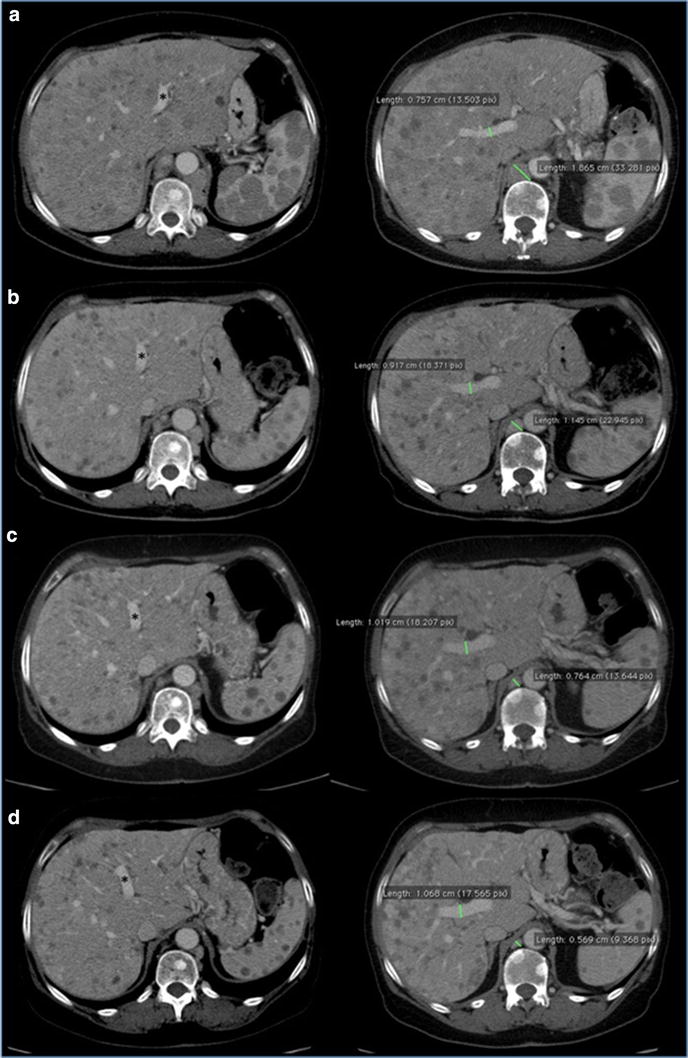

Fig. 4.

Hepatomegaly reduction. CT portal-phase contrast-enhanced images: Coronal plane reconstruction and Axial Maximum Intensity Projection (MIP) reconstruction at time 0 (a) and at 4 (b), 7 (c), 10 month (d) follow up examinations. Progressive reduction of longitudinal diameter of the liver measured in the mid-clavicular line was observed at follow up study. Progressive reduction of lower margin extension below costal arch was also detected. Caudal displacement of right kidney at time 0 (white arrow) gradually disappears at successive studies. Axial MIP images show progressive reduction of the displacement effect on the portal bifurcation due to decrease of metastatic parenchymal lesions: space between left and right portal trunk (angle) gradually decrease over time. Note the increased caliber of portal trunks and progressive reduction of the swelling of liver profile (arrowhead) related with hepatomegaly, with increased thickness of perivisceral fat

Fig. 5.

CT portal-phase contrast-enhanced images of two different planes at time 0 (a) and at 4 (b), 7 (c), 10 month (d) follow up examinations. Conspicuous volume reduction of paraesophageal and paracardial lymph nodes was observed over time. Increased caliber of portal trunks was detected, due to parenchymal architecture changes, reduced mass effect and mild portal hypertension. Note progressive dislocation of left portal trunk asterisk from left to right side due to reduction of hepatomegaly. Also note volume decrease of liver and spleen lesions with gradually remission of parenchymal architecture

The patient continued the treatment and the total body CT-scan performed on January 2015 showed once again the persistence of the framework of further instrumental disease response, on lung, liver, and multiple lymphnodal metastases. Then, given the response both clinical and radiological and considering the improvement in quality of life and Performance Status achieved by the patient, we continued the treatment with temozolomide at the same dosage and regimen. In April 2015, the patient, stable for clinical conditions (PS = 0), with very good quality of life, performed a new total body CT-scan (Figs. 4, 5, 6) which showed an unexpected, further partial response. Treatment with TMZ is still ongoing.